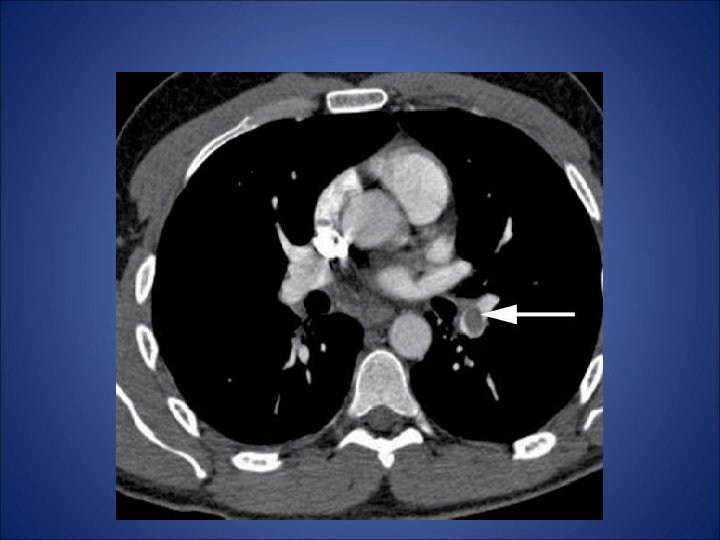

Embolism pulmonar acut • - desi simptomele clinice indica embolismul pulmonar (durere pleuritica, dispnee), pacientul din cazul de fata nu prezinta niciun factor de risc (chiar mai mult ca factori de preventie avem varsta si activitatea fizica) - pentru certitudine s-a folosit investigatia CT care a relevat multipli emboli atat in vascularizatia majora a plamanului stang cat si a celui drept - orice evaluarea ulterioara a pacientului nu a putut elucida cauza embolismului. • Nu exista suficiente referiri la naproxen in cazurile raportate de embolism pulmonar si astfel nu poate fi incriminat pentru producerea acestui fenomen. Mai mult, dupa tratamentul intraspitalicesc pacientul a refuzat tratamentul cu warfarina si la la cateva luni au aparut alte episoade de embolism. Decizia terapeutica finala a fost plasarea unui filtru Greenfield de vena cava inferioara.

TC abdominal